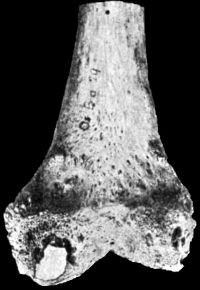

307 167.Lower End of Humerus from case of Cubitus Varus

309 168.Intra-Uterine Amputation of Forearm